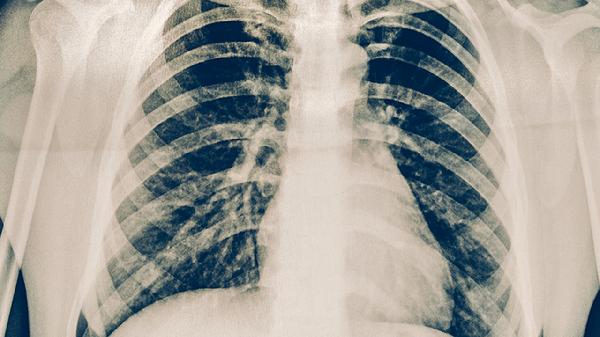

胸部X線可顯示肺結(jié)核典型病變?nèi)绶渭饨?rùn)、空洞形成或纖維鈣化灶。早期可能僅見(jiàn)斑片狀陰影,進(jìn)展期可出現(xiàn)多形態(tài)混合病灶。該檢查對(duì)肺外結(jié)核診斷價(jià)值有限,且需與肺炎、肺癌等疾病鑒別,通常需結(jié)合其他檢查明確診斷。